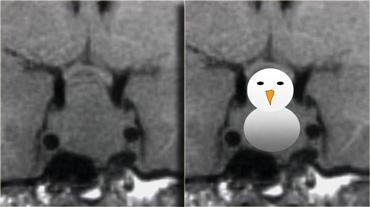

Do là các khối u mềm, chúng thường bị thắt lại tại màng hoành yên (diaphragma sellae), tạo nên hình ảnh ‘người tuyết’ đặc trưng.

Đây là một đặc điểm giúp phân biệt u tuyến yên đại tuyến với u màng não (meningioma).

Một đặc điểm khác có thể giúp phân biệt là sự giãn rộng của hố yên – điều này thường chỉ xảy ra với u tuyến yên đại tuyến có nguồn gốc từ trong hố yên.

Bên trái là một ví dụ khác về u tuyến yên đại tuyến.

Tổn thương bắt đầu từ hố yên, vốn đã bị giãn rộng, và lan rộng vào bể dịch não tủy trên yên (suprasellar cistern).

Lưu ý hình ảnh ‘người tuyết’ kinh điển được tạo ra do sự thắt nghẽn bởi màng hoành yên.

Chú ý mức dịch-máu (blood-fluid level), cho thấy có xuất huyết.